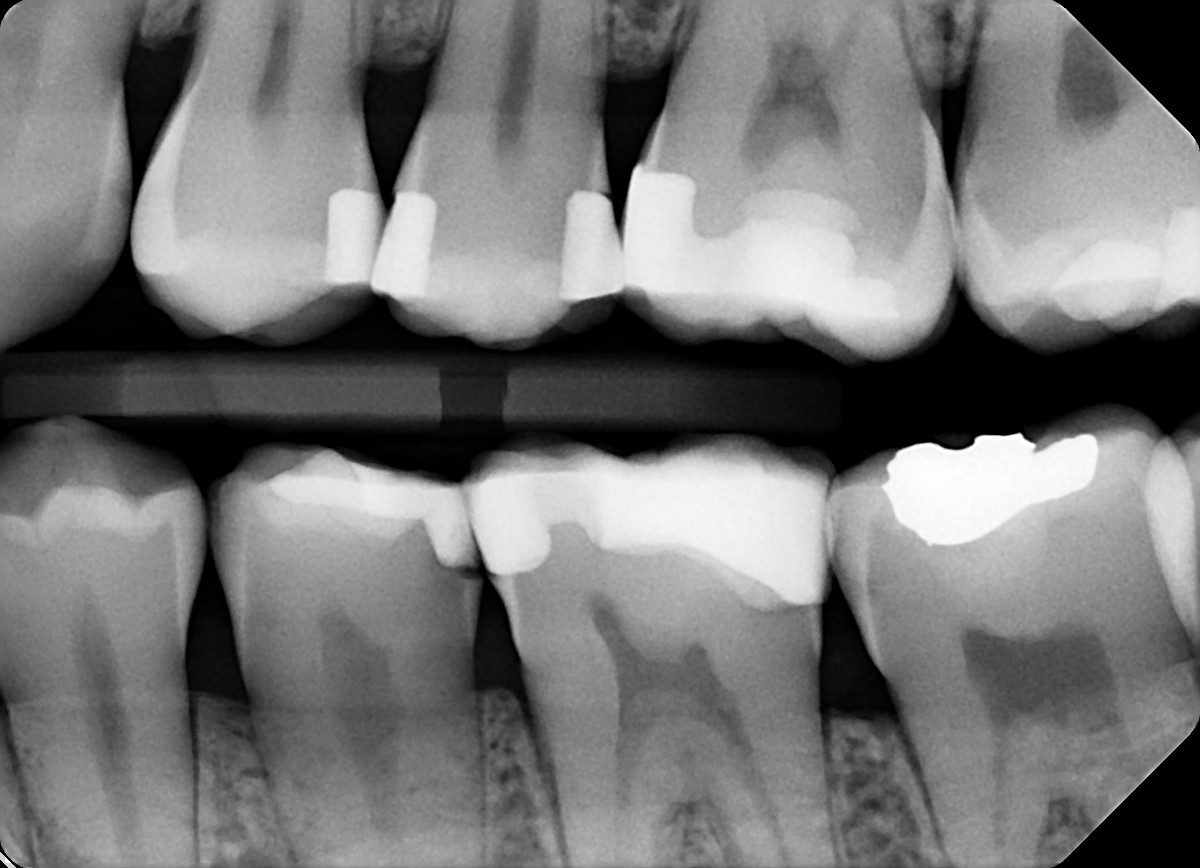

18. On which surface a recurrent caries can be detected?

crowns mostly show open margin not recurrent caries